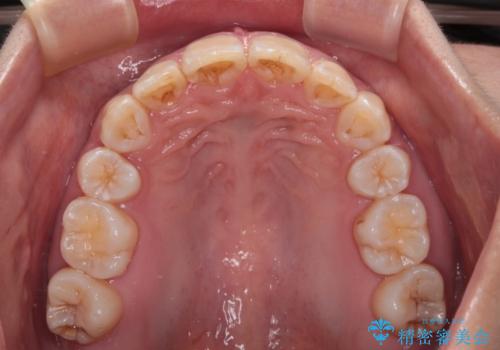

【モニター】出っ歯と八重歯 抜歯矯正でスッキリとした口元に

- 前方に飛び出した前歯と、下顎の八重歯を気にして来院された患者様です。

口元の突出感を改善するため、上下左右の第一小臼歯4本を抜歯し、ワイヤー装置にて矯正治療を行うこととしました。

抜歯矯正により、口元の印象だけでなく、横顔の印象も大きく改善されました。